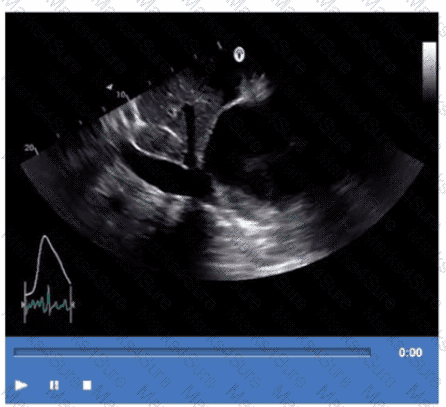

Which is the most likely abnormality represented in these images from a 48-year-old man with shortness of breath?